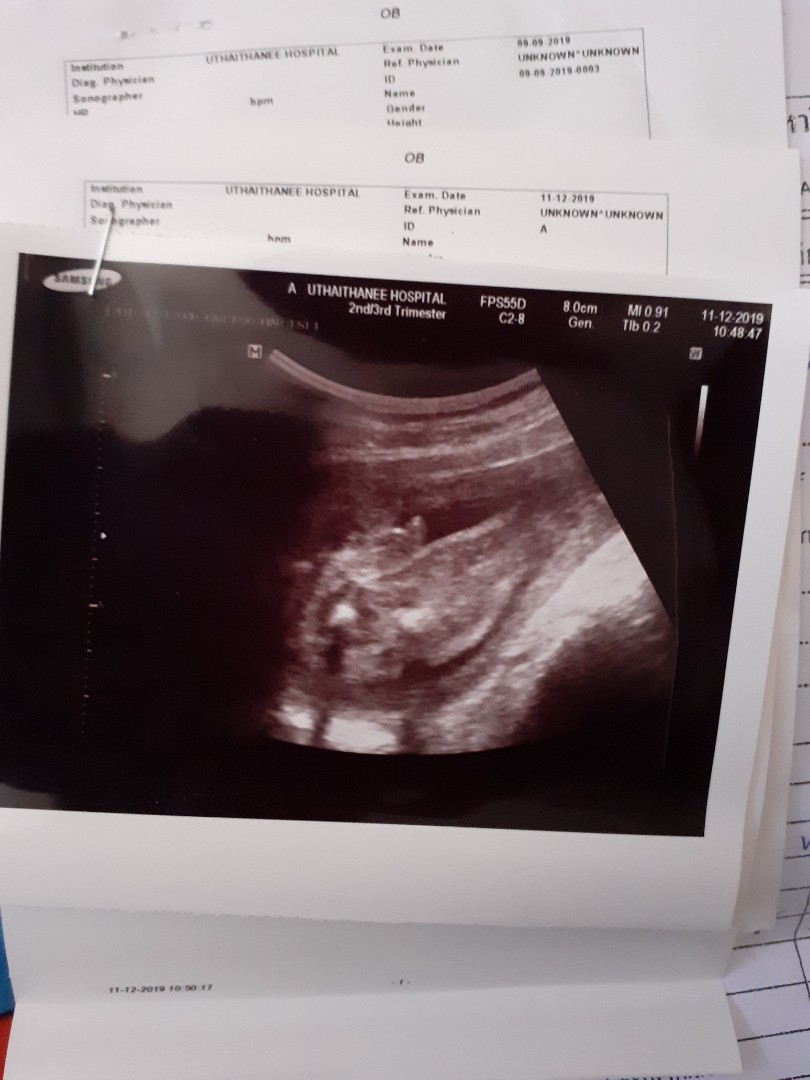

โชว์ผลซาวด์กันค่ะ

คุณลุงหมอบอกมีกลีบ?ใครมีกลีบ ใครมีแท่ง ลงมาอวดกันจร้า

ปู้จายคร๊าบบ😆😆

ผู้หญิงค่าา 👧 21 w

หนูมีกลีบค้าา😂

กลีบเต็มๆคะ